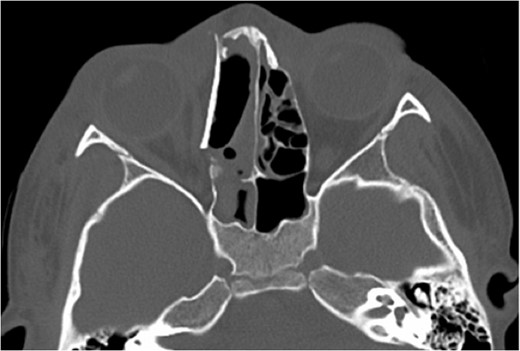

A 6-year-old boy with a background of asthma presented to a tertiary paediatric unit in May 2016 with a 3-day history of right eye pain, proptosis and erythema under the care of the ENT team. A provisional diagnosis of a periorbital cellulitis was made secondary to ethmoid sinusitis and management with intravenous antibiotics (ceftriaxone), intranasal steroids, saline douches and topical oxyxlometazoline was initiated. Ophthalmological assessment demonstrated normal colour vision, acuity and light reflexes bilaterally but also proptosis-related ophthalmoplegia. Computed tomography (CT) imaging of the orbits and paranasal sinuses demonstrated complete opacification of the right-sided paranasal sinuses and compromise of the right frontal and ostiomeatal unit. In addition there was an expansile abnormality centred on the ethmoidal labyrinth with bony remodelling of the lamina papyracea and a subperiosteal collection adjacent to the medial orbital wall (Figs 1 and 2). The most likely diagnosis was felt to be an infective process with mucopyocele formation complicated by a subperisoteal post-septal collection. An MRI scan with gadolinium of the orbits and sinuses confirmed the unilateral pattern of sinus opacification within the right frontal, ethmoids and maxillary sinus. The lesion demonstrated multiple fluid–fluid levels and peripheral enhancement (Figs 3 and 4). The patient was treated by endoscopic drainage of the lesion, which revealed only blood. He initially had some improvement of his proptosis but recurred within a few days and so further, more extensive endoscopic debridement was performed.

Axial T1 post-contrast sequence with fat suppression demonstrating peripheral enhancement (white arrows) but no internal or solid enhancing components to suggest that this is a secondary ABC.

At this point the MRI was reviewed and the possibility of an ABC was raised. This was due to the presence of fluid–fluid levels, cyst within a cyst appearance and lack of restricted diffusion within the sinonasal contents and material drained at the time of the first endoscopic procedure. He was discharged home on oral co-amoxiclav, and topical betamethasone nose drops.